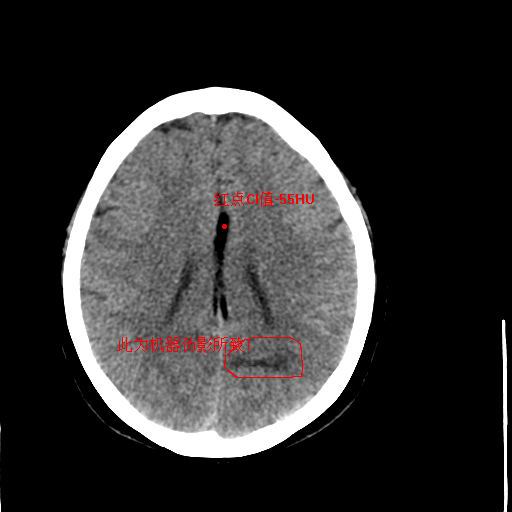

病人资料:女,57岁,反复头痛6年余,无恶心、呕吐等症状,体查:bp180/100mmhg。

中线脂肪瘤

胼胝体发育不良并脂肪瘤形成,脂肪瘤形成是因,胼胝体发育不良是果。如果正规些应该是中线脂肪瘤并胼胝体发育不良!

典型中线脂肪瘤

胼胝体发育不良

中线脂肪瘤并胼胝体发育不良。

形态 范围都像伪影